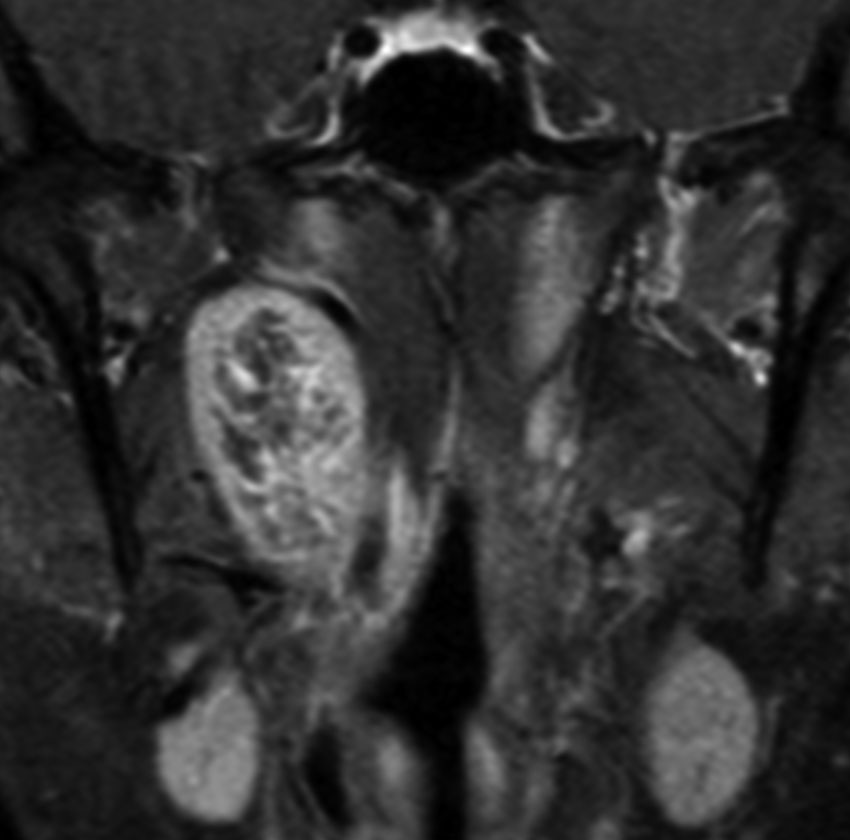

症例:頸静脈孔から頭蓋内へのもの

頸静脈孔を中心に頭蓋底骨の破壊 erosionがみられます。小脳延髄角部に進展して延髄を圧迫しています。聴神経を圧迫して聴力低下で発見された,迷走神経鞘腫です。頸静脈孔内発生のものは脳槽内の迷走神経根から腫瘍を剥離することができます。

手術直後のMRIです。頸静脈孔より深い位置にある腫瘍まで摘出しようとすると,舌咽,迷走,副神経を損傷しますから,最深部の部分だけ残して摘出しました。

手術後14年が経過しますが,無治療で残存腫瘍は縮小しました。術後神経鞘腫の自然経過ではよく観られることです。

ですから,無理して全摘出しない。